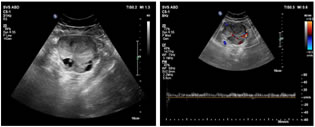

A 40 years old nulliparous premenopausal woman, presented to the gynaecology OPD with a chief complaint of abnormal uterine bleeding and pain in the lower abdomen, predominantly towards left side since an year. The patient had no significant relevant past history or risk factors. The clinical examination of the abdomen revealed no palpable mass. Abdominal ultrasound revealed a solid heterogeneously hypoechoic mass lesion arising from the left ovary, measuring approximately 55x53x50mm and showing moderate colour flow on colour doppler. A moderately enlarged uterus with increase in endometrial thickness was also identified (24 mm). No suspicious abdominal lymphadenopathy was noted. MRI Pelvis showed a single large well defined moderately enhancing, mixed predominantly solid lesion measuring approximately 60x58x53mm (MLXCCXAP) in the left adnexa, which is heterogeneously hypointense on T1W, Isointense with central hypointense areas on T2W, heterogeneously hyperintense with central hypointense areas on T2W/STIR and showing no restricted diffusion on DWI. Uterus appears moderately enlarged with multilobulated heterogenous diffuse moderately enhancing solid areas and non-enhancing cystic areas within the endometrial cavity. No suspicious pelvic lymphadenopathy was noted. Serum CA-125 concentration was elevated,95 U/mL (normal range <35 U/mL). After the positive frozen section pathological examination of the left ovary, the patient underwent a total abdominal hysterectomy, bilateral salpingo-oophorectomy, bilateral pelvic and para-aortic lymphadenectomy, and omentectomy. Pathological findings revealed a well-differentiated endometrioid carcinoma of the left ovary and a well-differentiated endometrioid carcinoma of the endometrium. The patient did not receive any adjuvant chemotherapy or radiotherapy and was suggested for a regular follow-up. Up to the last follow-up visit (April 2021), the patient had no recurrence.

Figure 1                                             Figure 2

Figure 1: Mixed predominantly solid, heterogeneously hypoechoic mass lesion in the left adnexa; Figure 2: Mass lesion showing moderate vascularity on application of colour Doppler; Figure 3: Increased endometrial thickness with multilobulated heterogenous diffuse solid areas and cystic areas; Figure 4: Few solid components showing mild vascularity on application of colour Doppler;